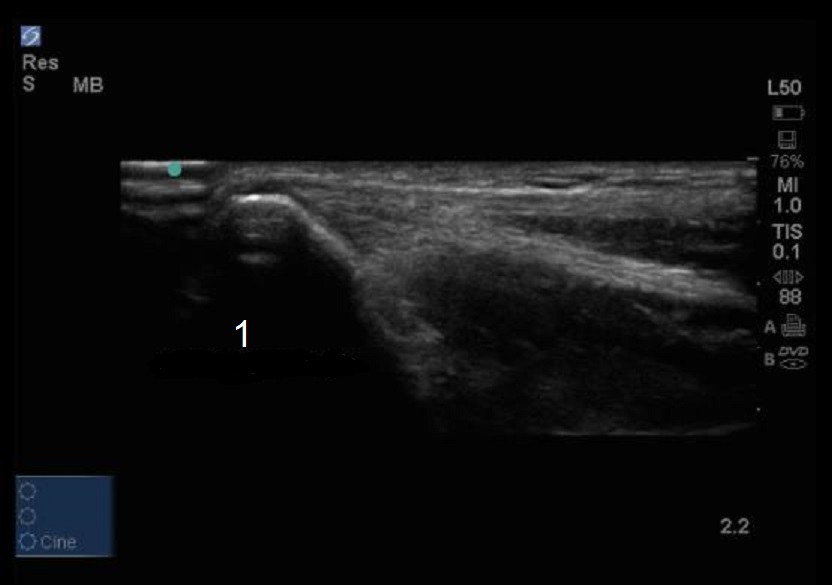

Elbow Medial Epicondyle Flexor Tendons Image

Medial Epicondyle